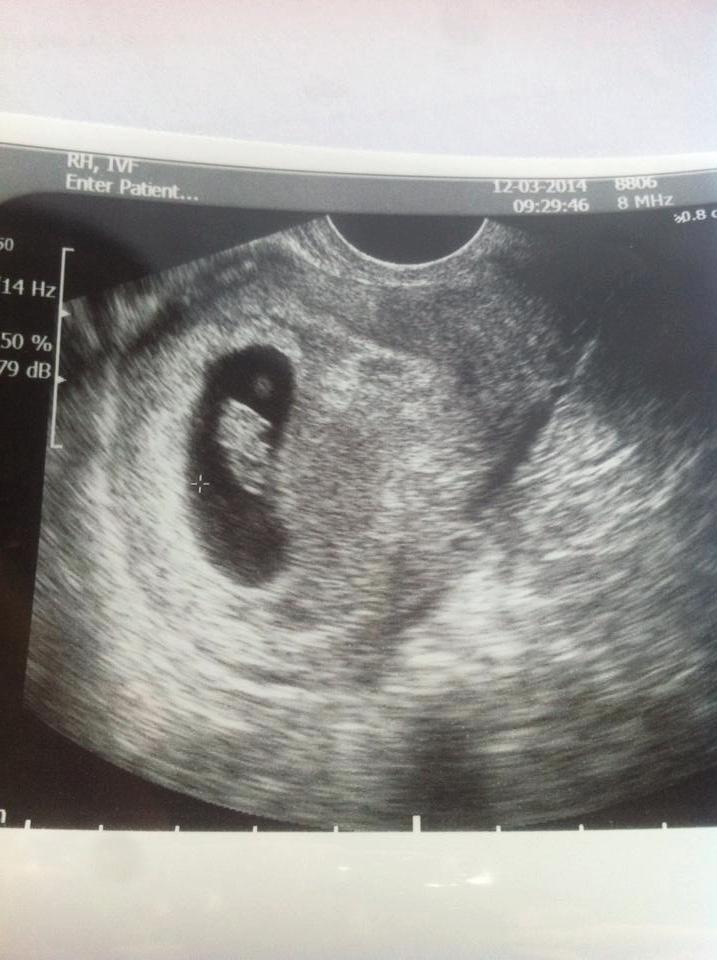

Jaaaaaaaa Lykke! Lille spiren sitt hjerte dunket så flott og er nå 16 mm stor :) Nye termindato ble 26.10.2014 ;) Så var ganske så likt som jeg trodde :) Vis vedlegget 53483